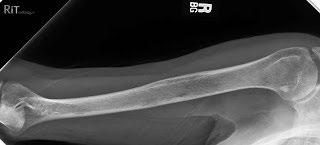

Testing For Myeloma: Imaging

Imaging:

– Skeletal survey: Series of X-rays; less sensitive than other techniques

– Whole body low dose (CTWB-LD CT )

– Positron Emission Tomography (PET/CT)

– Magnetic Resonance Imaging (MRI)

Healthy bone versus myeloma bone disease

This Photo by Unknown Author is licensed under CC BY-NC-ND